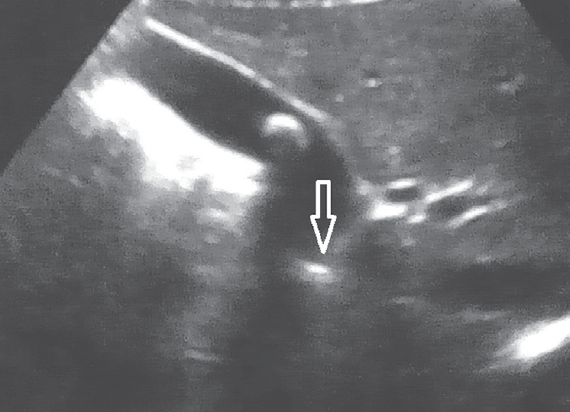

Research result. All patients with cholelithiasis identified different ways deformation in the area of gallbladder duct. One of the major causes of cholelithiasis in children are changes in the gallbladder duct. No patient has ever been found in concretions extrahepatic biliary passages. In patients with chronic stone-free cholecystitis pathology in the area of bladder flow was not found.